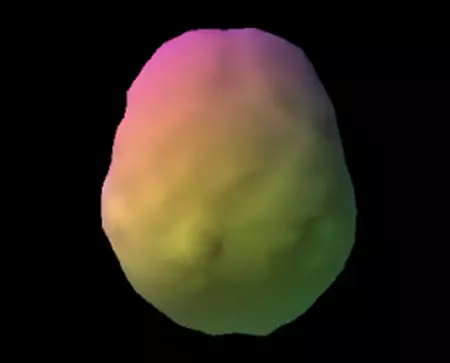

Healthy Brain Scan

SPECT (single photon emission computed tomography) is a nuclear medicine study that evaluates blood flow and activity in the brain. Basically, it shows three things: healthy activity, too little activity, or too much activity. The healthy surface brain SPECT scan on the left shows full, even symmetrical activity. The concussion scan on the right reveals unhealthy “holes” (areas that represent low blood flow and activity) in the damaged area..